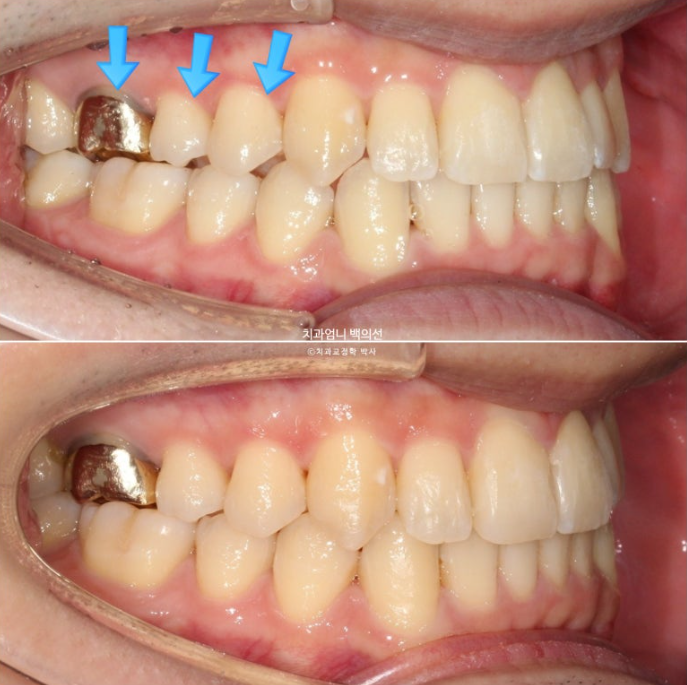

2주 후

2주간 마지막 인비절라인 장치의 어금니 부분을 잘라내고 잘때만 끼면 사진과 같은 변화가 나타납니다 어금니에 타이트하고 이븐한 교합이 자연스레 형성됩니다.

파란 화살표 부분이 치료 마무리 직후 논문대로 어금니 교합이 0.9mm떠있는 상태로 보시면 됩니다.

아래 사진은 2주간 교합 안정화 과정을 거쳐서 어금니가 잘 닿게된 모습입니다.

특히 환자분은 교정 후 가철식 유지장치로 비베라를 원하였는데 비베라 제작을 위해 먼저 어금니 교합 안정화가 반드시 선행되어야 합니다 어금니가 뜬 상태로 비베라가 제작되면 안되겠죠.